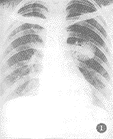

2.2.3 瘤体影像特征 X线表现呈球型10例(左肺4例,右肺6例);团块状20例(左肺6例,右肺14例)。球型的X线特征是:肿块大多呈圆形,椭圆形,大小1~4 cm不等,边缘光滑,密度均匀,轮廓清楚(图1)肿块周围多有假性包膜。团块型的特征是:病灶大小形态不一,密度多不均匀,边缘模糊,境界不清,有的形似大片渗出的炎性阴影(图2,3)或在肿块周围形成“外套”性炎症。4例可见明显的长毛刺,6例体层片上显示肿块内侧缘与肺门之间牵拉的索条影,2例形成压迫性肺不张,1例瘤体形似“倒雪人”状(图4)。

图1 左上肺见一5 cm×5 cm大小实质性肿块,边缘光滑、密度均匀、包膜完整,病理证实肺炎性假瘤

3.3 影像学表现:肺炎性假瘤可发生在两肺的任何部位,本组右上肺(12/20)多于左上肺(2/10)。位于下叶的假瘤多位于下叶背段和内后基底段。球型瘤体一般边缘光滑锐利,直径多在1~4 cm,密度比较均匀,周围肺野清晰。团块样的瘤体一般境界不清,边缘模糊,部分病灶密度浓淡不匀,如多次并发急性炎症,可造成“瘤”影扩大,在其周围恰似炎性浸润的片状影。因此,假瘤边缘清楚与否取决于肿块周围的病理变化,境界面清楚者瘤体周围一般有假性包膜。若病灶处于急性阶段时,假瘤周围显示炎性渗出,在瘤体周围多呈模糊影,亦无假包膜形成。本组1例呈“堆雪人”状,这是由于假瘤生长不规则所致。3例假瘤跨叶生长的原因,可能是跨叶浸润的炎症使得假瘤跨叶融合的结果[1,4]。